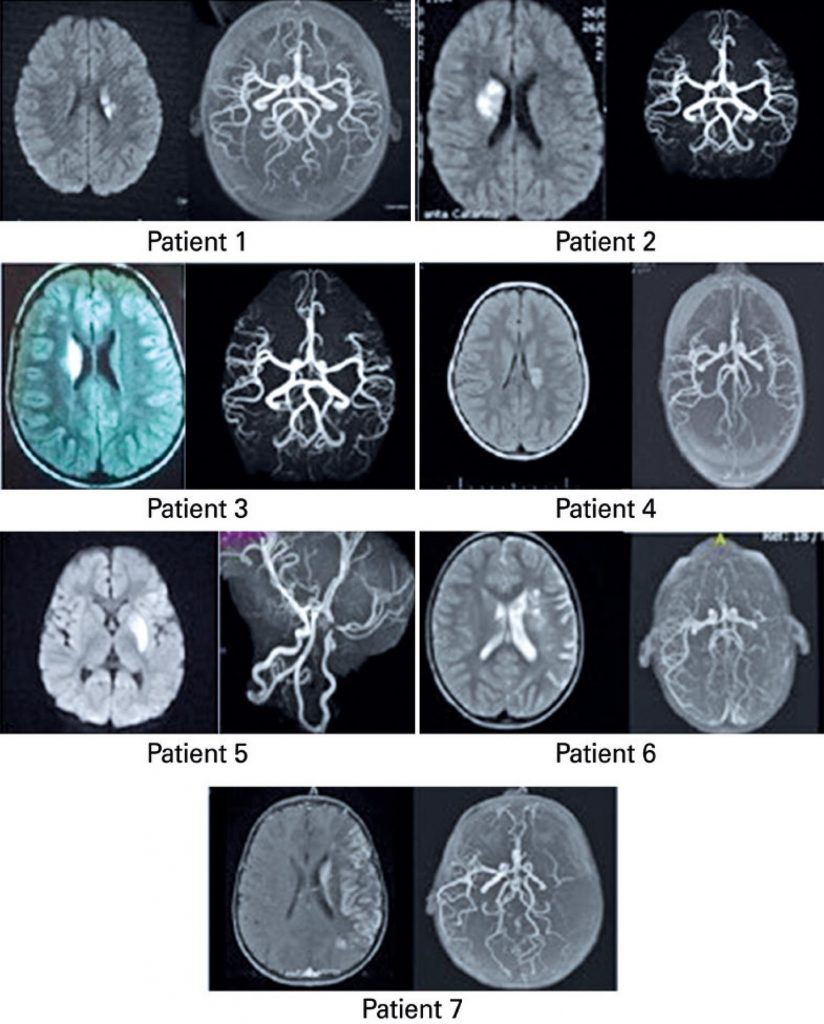

Seven children presenting with arterial ischemic stroke after varicella were evaluated at pediatric emergency services in the city of São Paulo (SP), Brazil. Ischemic stroke was determined by magnetic resonance imaging/magnetic resonance angiography in a topography compatible with the areas supplied by the middle cerebral or internal carotid arteries. IgG-class antibodies against varicella zoster virus and varicella-zoster virus DNA by polymerase chain reaction in cerebrospinal fluid were tested. Patients with prothrombotic conditions were excluded. The Pediatric Stroke Outcome Measure was applied upon admission and 4-years after the stroke.

All patients (age range: 1.3 to 4 years) included presented chickenpox 5.1 (±3.5) months before. All patients had analysis of anti-varicella-zoster-virus-IgG in cerebrospinal fluid, but only three (43%) had a positive result. Of the patients 43% had no vascular lesions identified in magnetic resonance angiography. All patients showed improvement in their sequela scores. After 4 years, five patients displayed good evolution in the Pediatric Stroke Outcome Measure, and only one patient presented with a score of 2 in the sensorimotor and cognition areas. No recurrence of arterial ischemic stroke was observed.